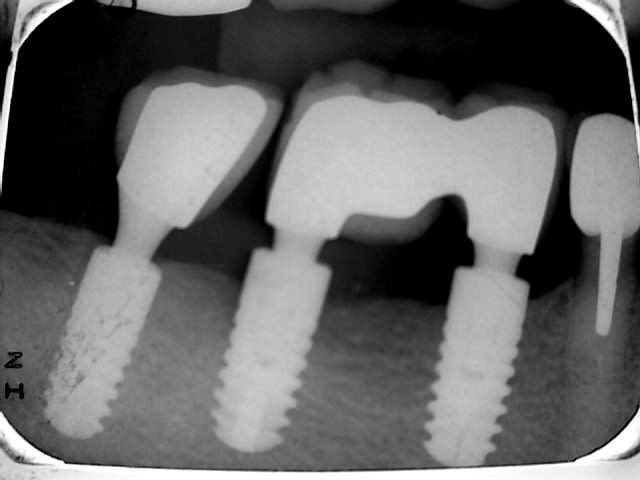

Quel est selon vous la marque de cet implant ?

Ankylos

Les deux anterieurs auraient du être posés en sous-crestal.

Regarde la différence avec le distal.

Cette radio est très démonstrative de l'intérêt de la pose en sous-crestal.

On voit bien l'os qui recouvre la plate-forme sur le distal.

Et la craterisation des autres...